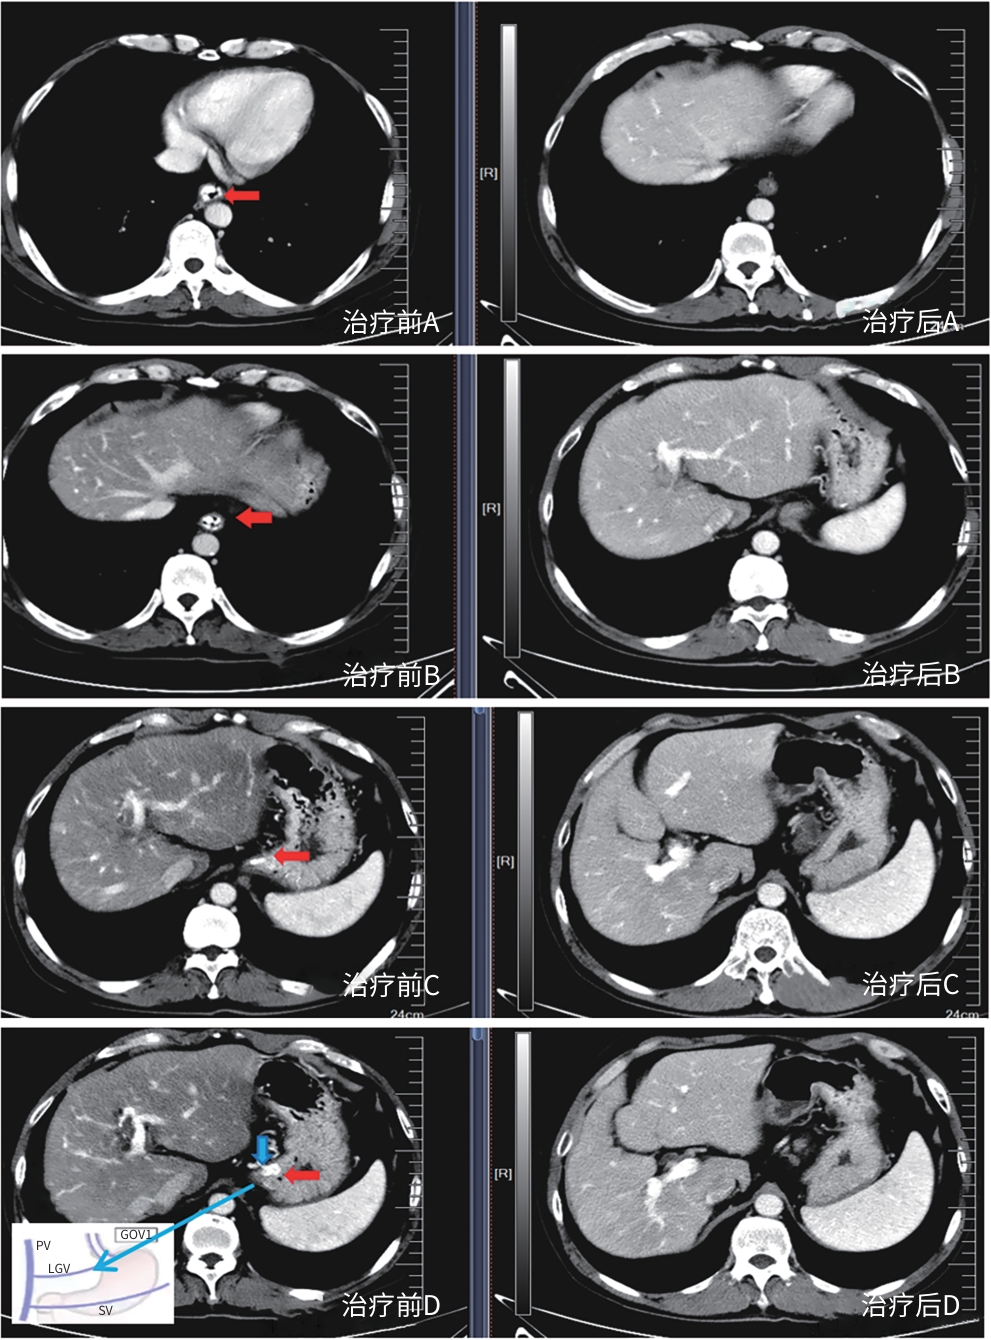

Safety and efficacy of puncture cyanoacrylate selective seal under endoscopic ultrasound versus traditional endoscopy in treatment of gastroesophageal varices: A randomized controlled trial

Jiali MA, Lingling HE, Hongshan WEI, Ping LI, Xiuxia LIANG

2025, 41(6): 1113-1119. DOI: 10.12449/JCH250617

Abstract(1013) HTML (176) PDF (1855KB)(56)

Abstract:

Objective  To investigate the safety and efficacy of puncture cyanoacrylate selective seal (PCSS) under endoscopic ultrasound in the treatment of gastroesophageal varices (GOV).  Methods  A total of 100 patients with liver cirrhosis who underwent endoscopic therapy for the secondary prevention of GOV bleeding in Beijing Ditan Hospital, Capital Medical University, from March 1 to December 31, 2023 were enrolled and randomly divided into PCSS group and traditional endoscopy group. The patients were followed up for 6 months after surgery, and the two groups were compared in terms of clinical outcome and complications. The primary outcome measure was the rate of alleviation or disappearance of GOV, and the secondary outcome measure was variceal rebleeding and death. The independent-samples t test was used for comparison of normally distributed or approximately normally distributed quantitative data between two groups, and the Wilcoxon non-parametric test was used for comparison of non-normally distributed quantitative data between two groups; the chi-square test or the Fisher’s exact test was used for comparison of qualitative data between two groups.  Results  There were 50 patients in the PCSS group, among whom 1 patient was lost to follow-up, and there were 50 patients in the traditional endoscopy group, among whom 3 patients were lost to follow-up. There were no significant differences between the two groups in baseline data such as age, sex, Child-Pugh class, varices grade, and GOV typing (all P>0.05). Compared with the traditional endoscopy group, the PCSS group had significantly better results of the number of endoscopic treatment sessions (t=-15.671, P=0.001), the total amount of tissue adhesive used (t=-2.830, P=0.006), and the rate of alleviation or eradication of varices sclerosis (χ2=7.078, P=0.029). Both groups had low rates of postoperative rebleeding, adverse reactions, and complications, and there were no significant differences between the two groups (all P>0.05).  Conclusion  Compared with traditional endoscopy, PCSS can significantly enhance treatment outcome while maintaining safety standards.